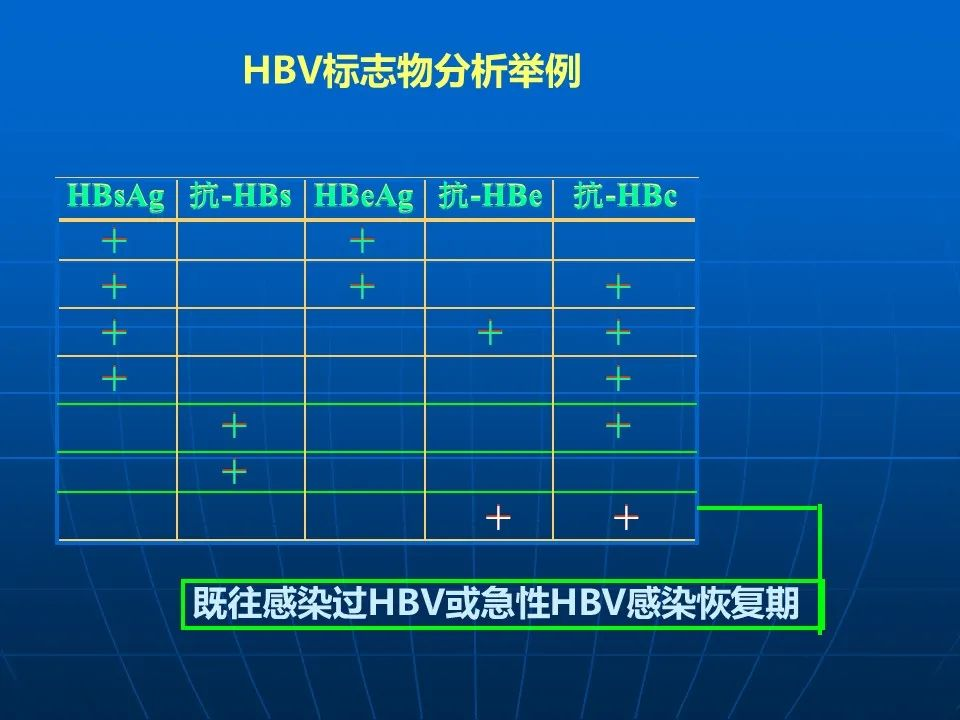

WBC:2.98*109/L;RBC:4.38*1012/L;PLT:91*109/L。免疫学HbeAb(+),HbcAb(+)。

可疑肝炎病史。